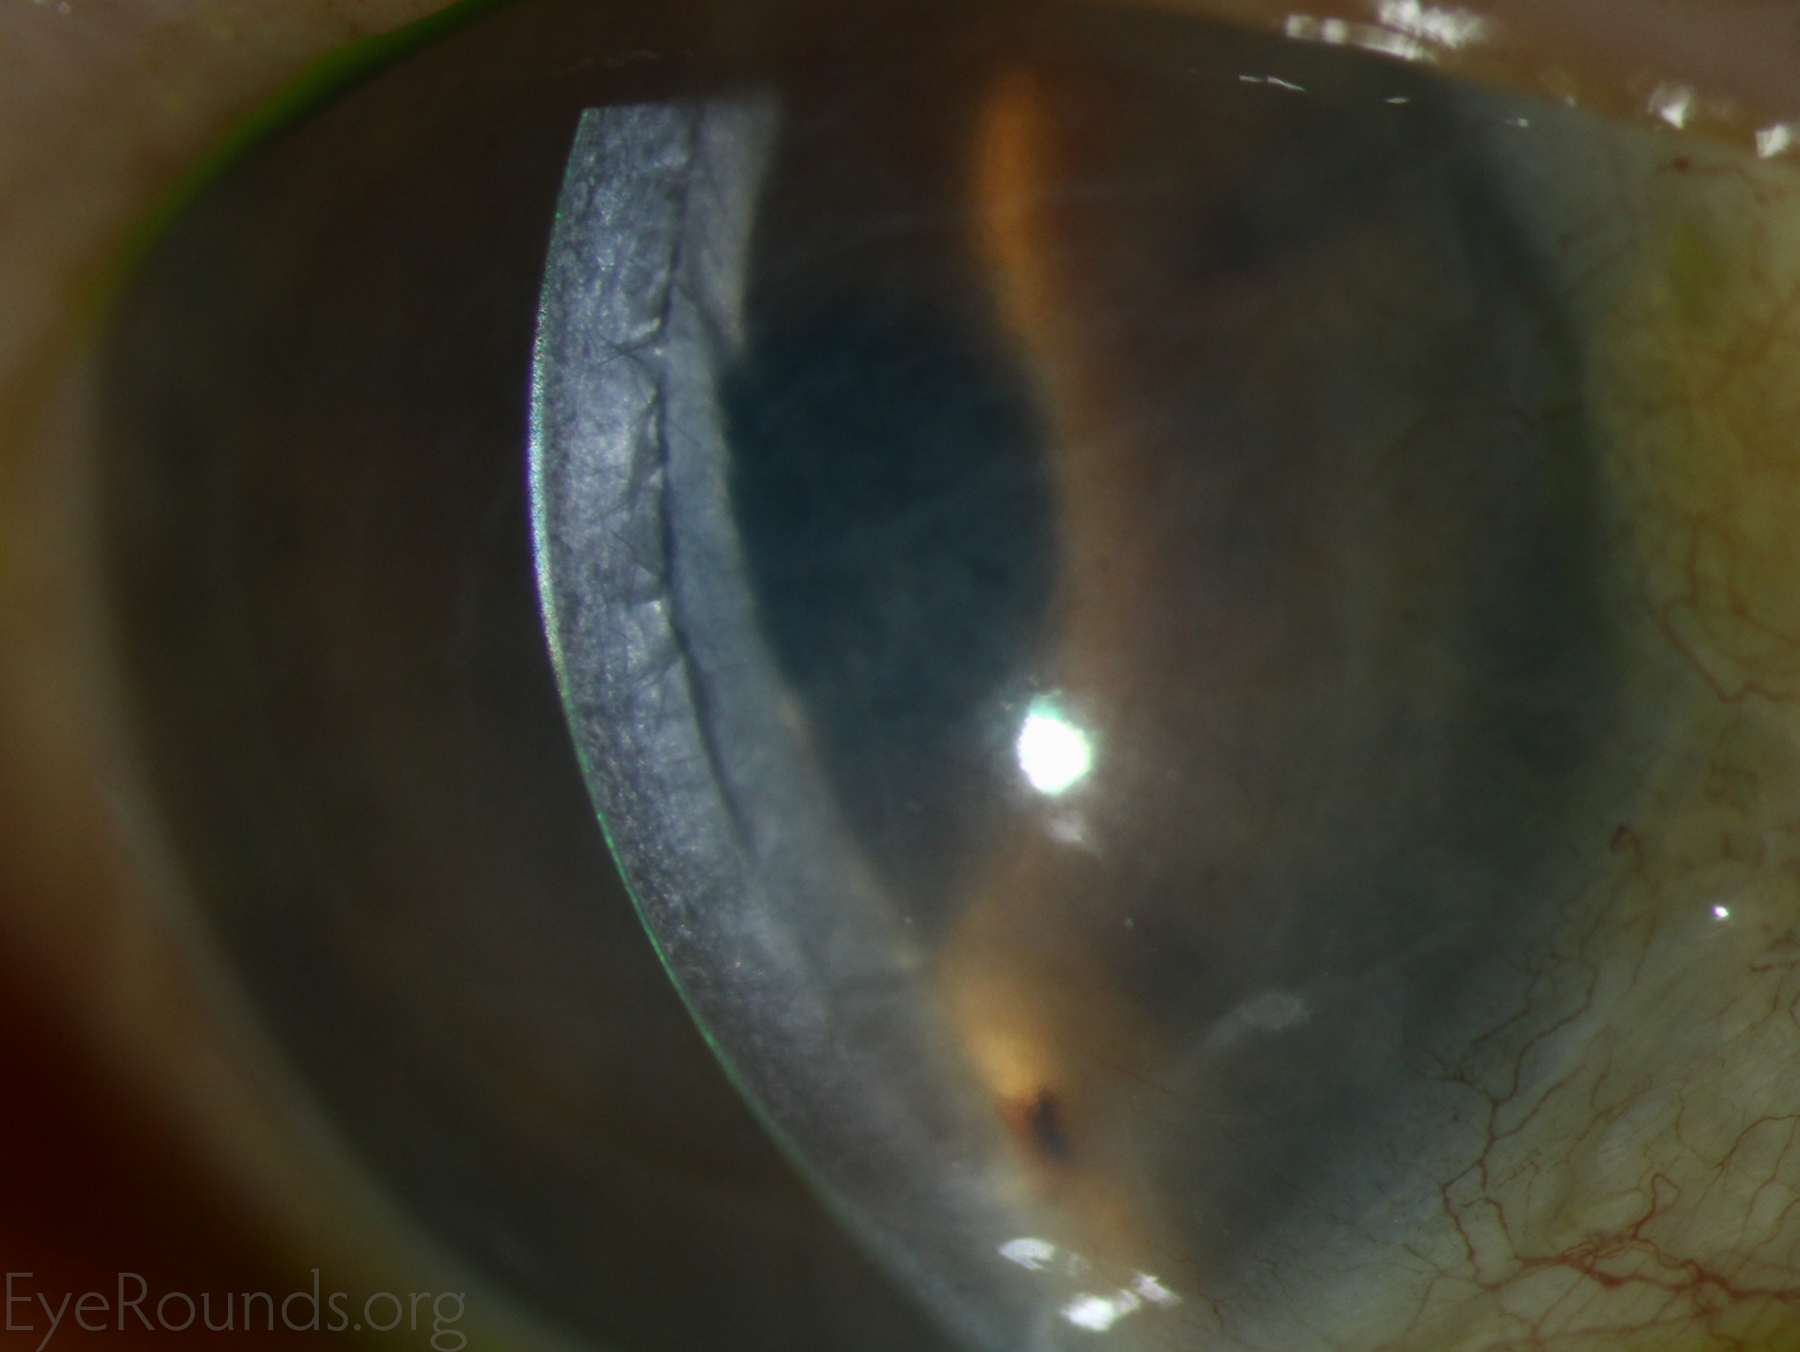

Because of thinness, fragility, and its characteristic scrolling properties (with the endothelium facing outward), the donor tissue can be difficult to handle and contribute to technical difficulties with the procedure. There is a higher risk of graft edge lifts (Figure 13) compared with DSAEK, sometimes requiring a re-bubble procedure.

Corneal transplantation is regarded as the most successful solid organ transplantation procedure (1). Niziol et al. performed a study in 2013 with follow-up averaging 10 years and found that corneal rejection after PK for keratoconus occurred in 44% of grafts, but only 8% of grafts actually failed (22). While long-term rejection data is not yet available for the newer EK procedures, lesser rejection rates have been demonstrated after DMEK (0.7%) and DSAEK (9%) than PK (17%) at 2 years in patients on the same postoperative steroid regimen and treated for similar indications (23). This may be secondary to reduced antigen load in the thinner graft tissue. Modern treatment efforts can account for the vast difference between graft rejection and failure. However, graft rejection still remains a significant cause of corneal graft failure (Figure 16) (1). The most effective intervention is early recognition and prompt treatment with topical steroid drops. If the patient notices any redness, pain, or decreased vision, it is critical to seek prompt treatment to maximize chances of reversing the rejection episode.